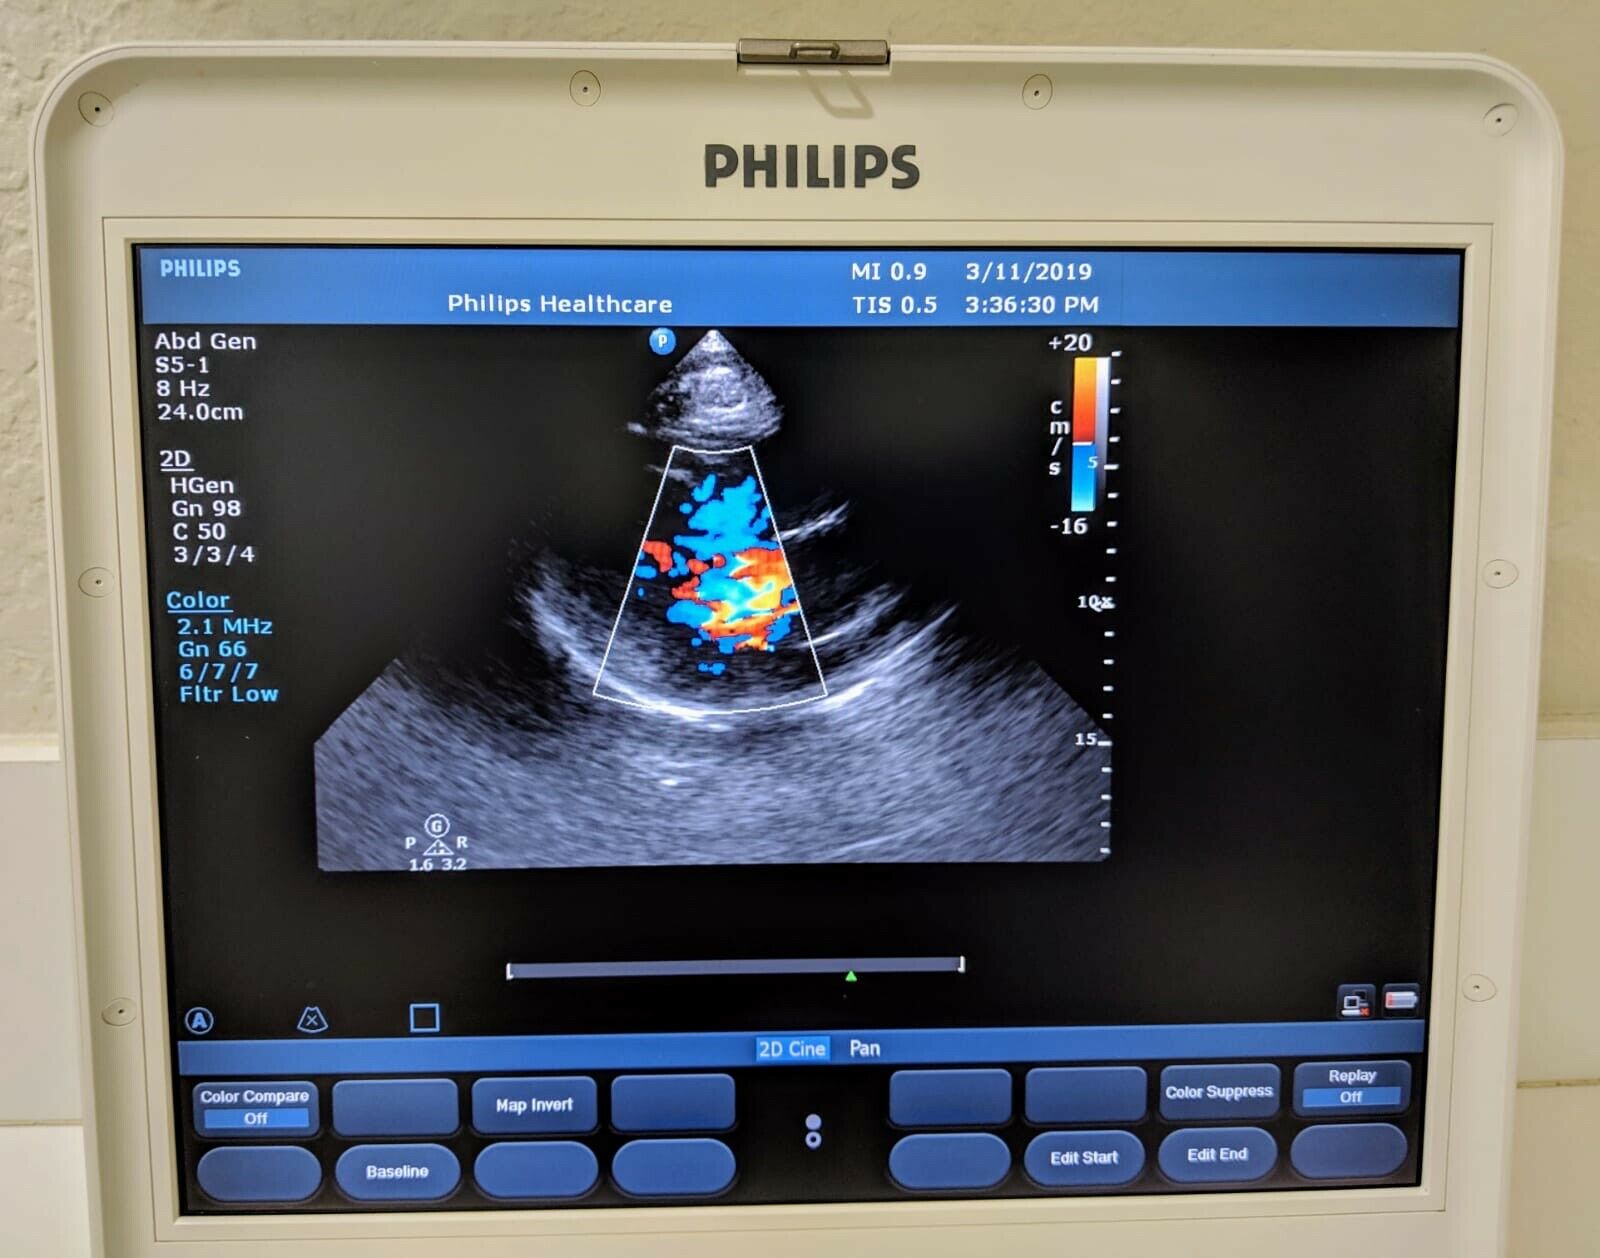

The Philips CX50 2013 Rev 4 Portable Ultrasound System with three probes is a high-performance imaging solution designed for flexibility across a range of clinical applications. This compact, portable ultrasound machine delivers premium imaging quality, making it ideal for point-of-care, cardiology, vascular, and emergency medicine. Equipped with Philips’ advanced imaging technologies like PureWave crystal technology, the CX50 provides exceptional resolution and detail, even in difficult-to-image patients.

The three included probes offer versatility, allowing clinicians to perform various exams, from cardiac and vascular to abdominal and superficial imaging. Its portability and lightweight design make it easy to transport between departments or use in field settings, without compromising on diagnostic accuracy. The CX50’s intuitive interface and customizable presets streamline workflows, making it user-friendly for fast-paced environments. This system is an excellent choice for healthcare providers needing a portable ultrasound solution that offers advanced imaging capabilities and multi-specialty support.